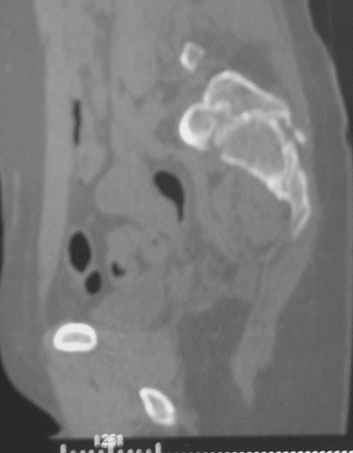

Травма 21.августа 2005г. На девочку в лесу упала береза. Доставлена в ближайшую ЦРБ. При поступлении установлен диагноз: Травматический шок 2-3 ст. Тупая травма живота. Забрюшинная гематома. Перелом костей таза с нарушением целостности тазового кольца. Перелом лонной и седалищной костей справа. Перелом поперечных отростков L3 - L5. Разрыв КПС справа. При поступлении выполнена диагностическая лапароскопия — выявлена обширная забрюшинная гематома. Было наложено скелетное вытяжение за бугристости обеих б/берцовых костей, больная уложена в гамак. Через неделю скелетное вытяжение демонтировано, гамак снят. Девочка уложена в положение «лягушки». Контрольные рентгенограммы через 4 недели после травмы. Заподозрен перелом дужки L5. Больная 26 сентября 2005 г. переведена в областную больницу в отделение детской ортопедии. При поступлении в локальном статусе: пальпация и перкуссия остистых и поперечных отростков L4-5 болезненная. Пальпация костей таза б/болезненная. С-м натяжения слабо положителен. Осевая нагрузка положительная. Движения в т/б суставах ограничены, болезненны. C-м прилипшей пятки отрицательный. C-м Ларрея и Варнейля отрицательный. Периферическая гемодинамика не нарушена.Неврологический статус: вторичная двусторонняя радикулопатия L5-S1. 29 сентября произведена компьютерная томография позвоночника и таза.

Судя по томограммам, радикулопатия может быть из-за компресии "конского хвоста" смещенным крестцовым позвонком, это хорошо видно на втором слева снимке. Если этот сегмент будет нестабилен и будет сохраняться неврологическая симптоматика, придется оперировать. Если неврологическая симптоматика уйдет и перелом стабилизируется, то можно обойтись без операции.